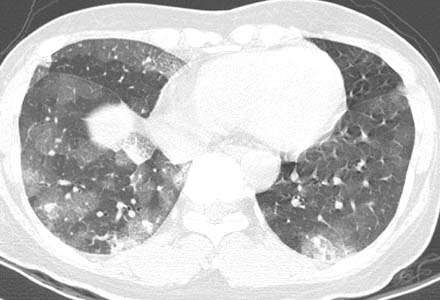

患者女性,43岁,肝癌tace治疗后出现胸闷不适.

请分析肺部改变的成因及可能的诊断.

动静脉瘘,栓塞剂经瘘口进入肝静脉--下腔静脉--右心房--右心室--肺动脉--沉积于肺内.

原发性肝癌进行栓塞治疗时,若肝动脉造影显示肿瘤侵犯肝静脉,且有明显的肝动静脉瘘,则使用碘油乳剂就不妥当,因为大量碘油可通过瘘道进入肺部,引起肺栓塞的并发症。

国内颜志平等报道:动物实验表明,碘化油进入肺部致死量约为0.5ml/ kg ,少量碘化油进入肺部可通过肺部吞噬细胞进行“消化”,故少量碘化油进入肺部后一般经过对症处理后,一般不会遗留明显并发症。